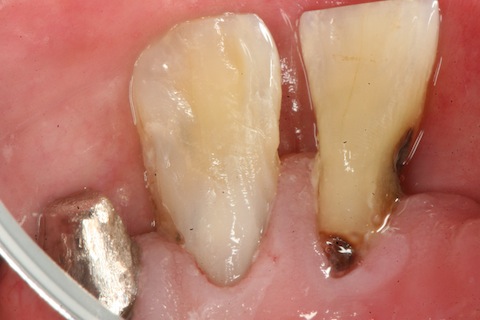

軟化象牙質を全部除去する必要はない。

α-TCPセメントで覆髄